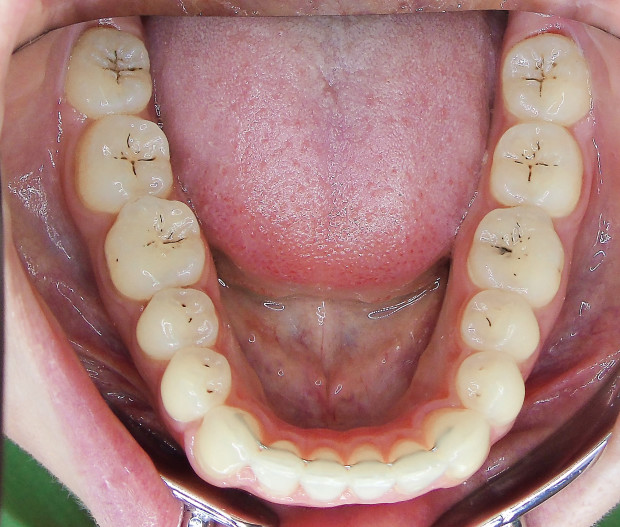

Der extraorale Befund (Abb. 1a–c) ergab ein gerades Durchschnittsgesicht mit leicht vergrößertem Nasolabialwinkel, ein symmetrisches Gesicht bei potenziell inkompetentem Lippenschluss sowie einen dolichofazialen Gesichtstyp. Intraoral lag beidseits annähernd eine Angle-Klasse I mit frontal offenem Biss (–2,5 mm) sowie ein dental-transversal zu schmaler Oberkiefer vor, woraus ein Kopfbiss von 13 und 23 resultierte. Des Weiteren zeigten sich ein persistierendes viszerales Schluckmuster und eine Inkongruenz der Kiefermitten (Abb. 2a–e; Abb. 3).

Sechs Monate nach Abschluss der Therapie besteht weiterhin ein stabiles Ergebnis. Wie im Vergleichsbild (Abb. 5a–c) zu sehen ist, konnte die geplante vertikale Korrektur vollständig erzielt und die Mittellinie bis auf eine MLV von 1 mm nach rechts im UK korrigiert werden.

Somit kann gezeigt werden, dass auch ohne operativen Eingriff oder festsitzende Apparaturen in kürzester Zeit ein ästhetisch und funktionell zufriedenstellendes Ergebnis erzielt werden kann (Abb. 6a–c; Abb. 7a–e). Es wird daher nachvollziehbar dargestellt, dass bei entsprechender Indikation Aligner für die Behandlung frontal offener Bisse eine hervorragende Alternative zu den konventionellen Behandlungsmethoden sein können. Voraussetzung für diesen Therapieansatz ist ein motivierter Patient mit guter Compliance.